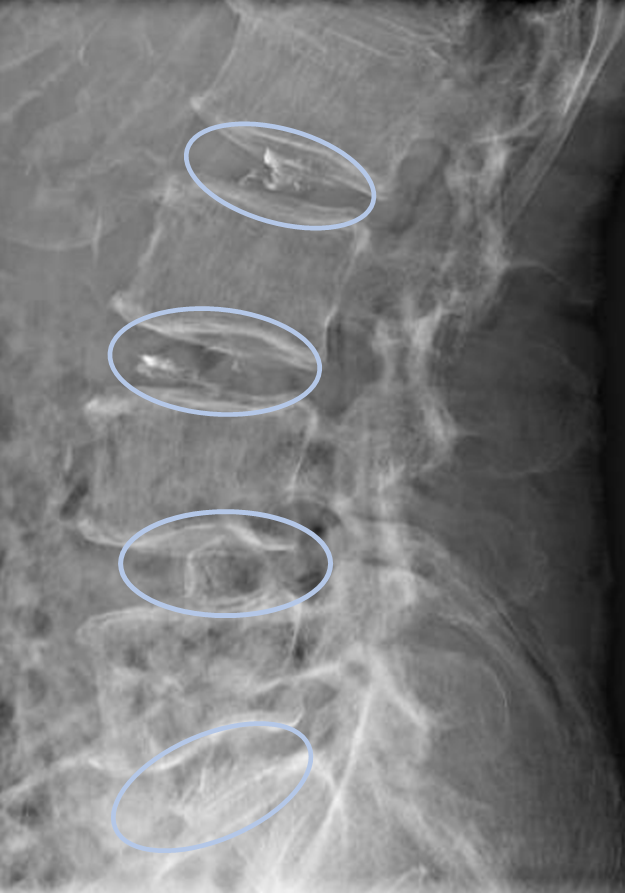

- L1/2,2/3,3/4,4/5,5/s-椎間板変性

以上の事が画像上認められます。

・L2/3,3/4,4/5,5/s-椎間板変性による椎間孔狭窄を認め、主症状の原因と考えられる。

DiscoGelを入れた後の画像になります。